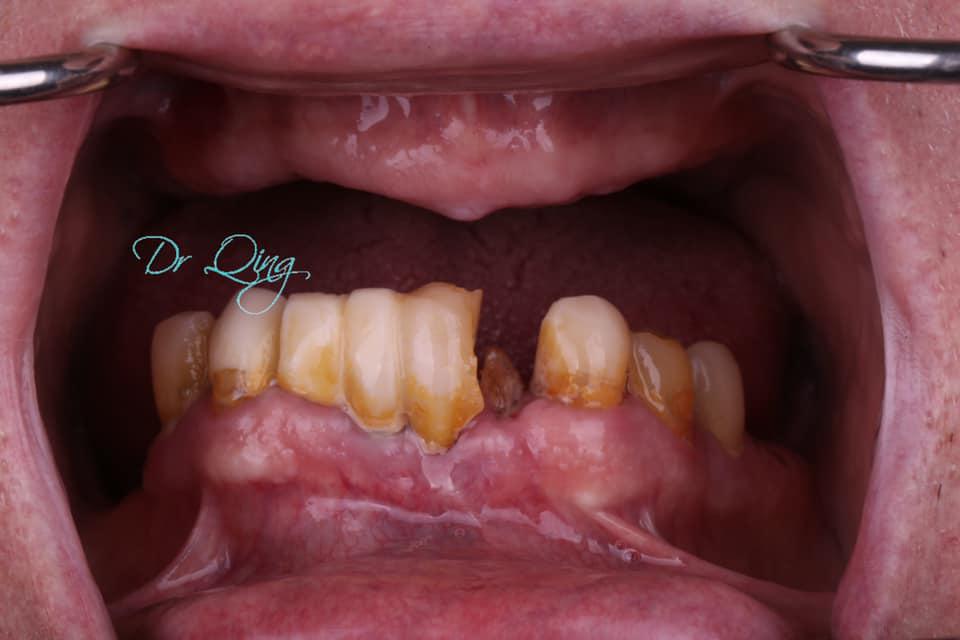

86-year old gentleman who has been suffering from missing teeth, reduced and uncomfortable chewing function, changing the diet from normal fibrous food to softer fatty and sugary food.

After several consultations and thorough examinations, Prosthodontist Qing office did pre-operatory digital design, simulation and treatment planning ( Fig 1 and 2) , the planing is the most important part to ensure a smooth execution and successful long-term outcome.

On last Friday morning 10am, we spent 1.5 hours for the minimally invasive surgery, and 3 hours to fabricate the new fixed teeth. About 4pm, the patient got the teeth and smile that he has been looking for a long time.